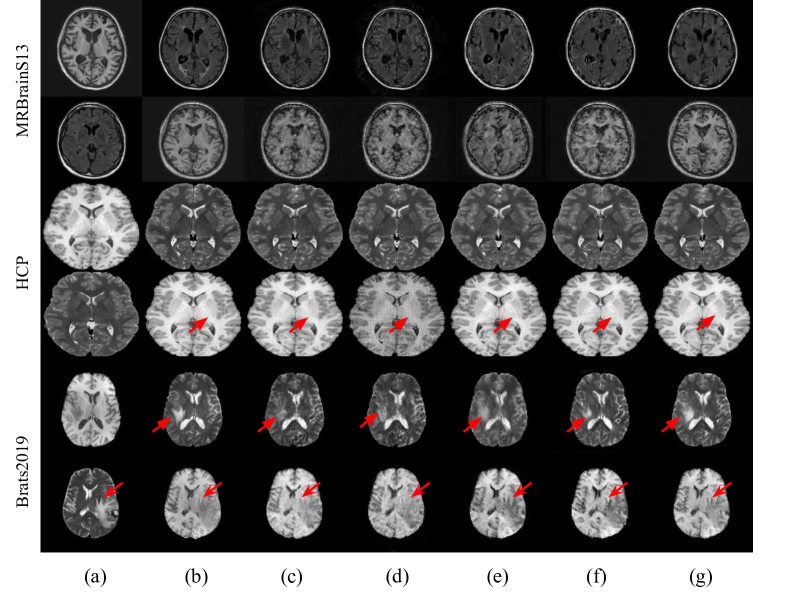

Refer to caption

Figure 4: A visualization of synthetic images on different datasets generated by (a) source image, (b) target image, (c) cycleGAN, (d) recycleGAN, (e) cycleflow, (f) alignflow, and (g) our method. Our method provides a good boundary on the tumor regions (red arrows in the fifth row) compared with the existing methods

Fig. 4 illustrates the image translation on different datasets. The proposed methods (in the last column) provided a better synthetic image, resulting in better MSE, SSIM and PSNR scores. For example, the proposed synthetic T2 image provides a high qualitatively difference along the tumor boundary (indicated by the red arrows in the fifth row) than in existing methods using the available source T1 image as input.